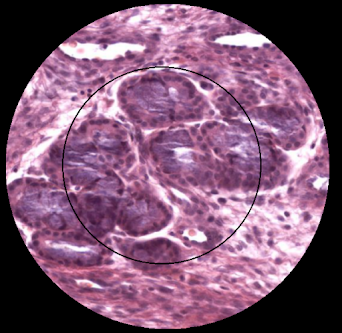

GLÁNDULAS SEROMUCOSAS NASALES.

Tomado de Histology guide

Encargadas de lubricar constantemente las paredes nasales, son inervadas por las fibras parasimpáticas del nervio facial destinada a la regulación del flujo sanguíneo a través de la mucosa. También encargadas de la producción de moco que será arrastrado por la actividad ciliar los ostium de drenaje. Esto permitirá la limpieza de estas cavidades.